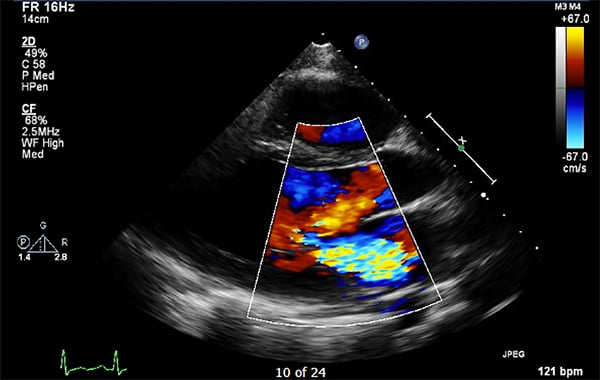

48-2 HOCM - Figure 2.png

Hypertrophic obstructive cardiomyopathy is the leading cause of non-traumatic sudden death in young individuals and most well-known for causing sudden cardiac death in athletes. While most known for b